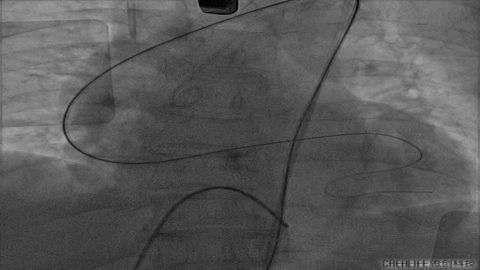

Nmued20预扩1

Nmued20预扩2

发生瓣叶切割,无窦侧瓣叶切割,Type0结构形变为类三叶瓣结构。